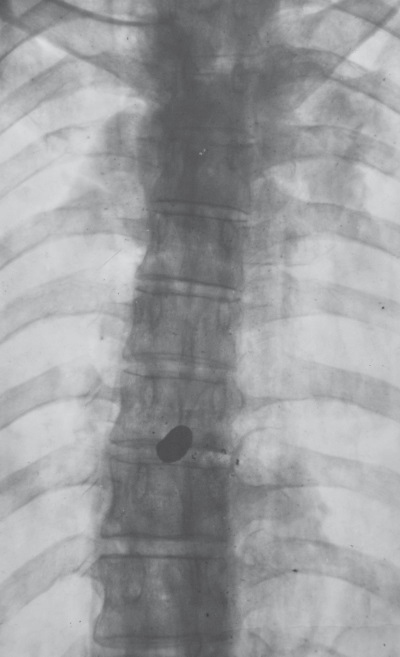

Я повиновался и оказался у монитора, который теперь преобразился. Все его пространство – если не считать нескольких иконок внизу, какие бывают практически на всяком мониторе – занимало изображение, и я сейчас же узнал рентгеновский снимок грудной клетки, а на нем меж тенями ребер виднелось прильнувшее к позвоночному столбу темное пятно, размером и формой напоминающее фасолину. Да, то ли я так и сказал: «Фасолина!», а то ли спросил: «А что это за фасолина такая?», и Бенавидес объяснил мне, что это никакая не фасолина, а сплющенная от удара о ребра пуля – одна из тех четырех, которыми 9 апреля 1948 года был убит Хорхе Эльесер Гайтан.

Кости Гайтана. Пуля, оборвавшая жизнь Гайтана. Я видел их, они были передо мной. Я понимал, что удостоился высокой чести. И подумал об уже мертвом лице Гайтана на знаменитом снимке и о том, как пришел в его дом в университетскую пору, когда начал интересоваться жизнью и смертью этого человека и их значением для нас, колумбийцев. Вспомнил застекленную витрину с костюмом-тройкой, который надел Гайтан в день своей гибели, и отверстия, оставленные в темно-синем сукне пулями Хуана Роа Сьерры. Одну из них я сейчас увидел в теле Гайтана. Бенавидес тоном хорошего преподавателя давал пояснения и комментарии, считал ребра и показывал невидимые внутренние органы, нараспев и наизусть, как стихи, декламируя целые фразы из протокола вскрытия. И одна из этих фраз – «не задета сердечная сумка и инфаркта следов никаких» – показалась мне достойной лучшей участи, но время сейчас явно было неподходящее для поэзии. Я мог лишь спрашивать себя, каким же это образом все это оказалось в руках Бенавидеса. А потом перестал спрашивать про себя и спросил про него, то есть вслух:

Иллюстрация к книге — Нетленный прах [i_003.jpg]